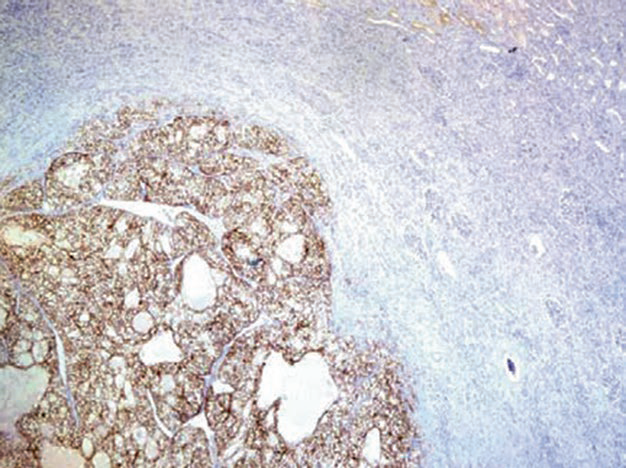

图1. 肾脏血管平滑肌脂肪瘤中,血管周围上皮样细胞表达HMB45。